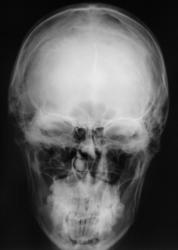

Как следует расценить "тень" на фоне клиновидной (основной) пазухи.

А  где прямая  проекция. Может это  сфеноидит.

Наверное, сфеноидит. Похоже, что клиновидная пазуха разделена сагиттальной костной перегородкой на две неравные части. Пневматизация бОльшей правой половины не нарушена. А левой - снижена. Вероятно, эта левая часть пазухи и дает неравномерное снижение пневматизации на боковой рентгенограмме. В любом случае, если у пациента головные боли, то вероятность сфеноидита ещё выше (неврологи, кстати, не всегда вспоминают про сфеноидит, когда пользуют пациентов с головной болью). А чтобы сфеноидит доказать без КТ, надо снять околоносовые пазухи с открытым ртом (извините за банальные рекомендации).